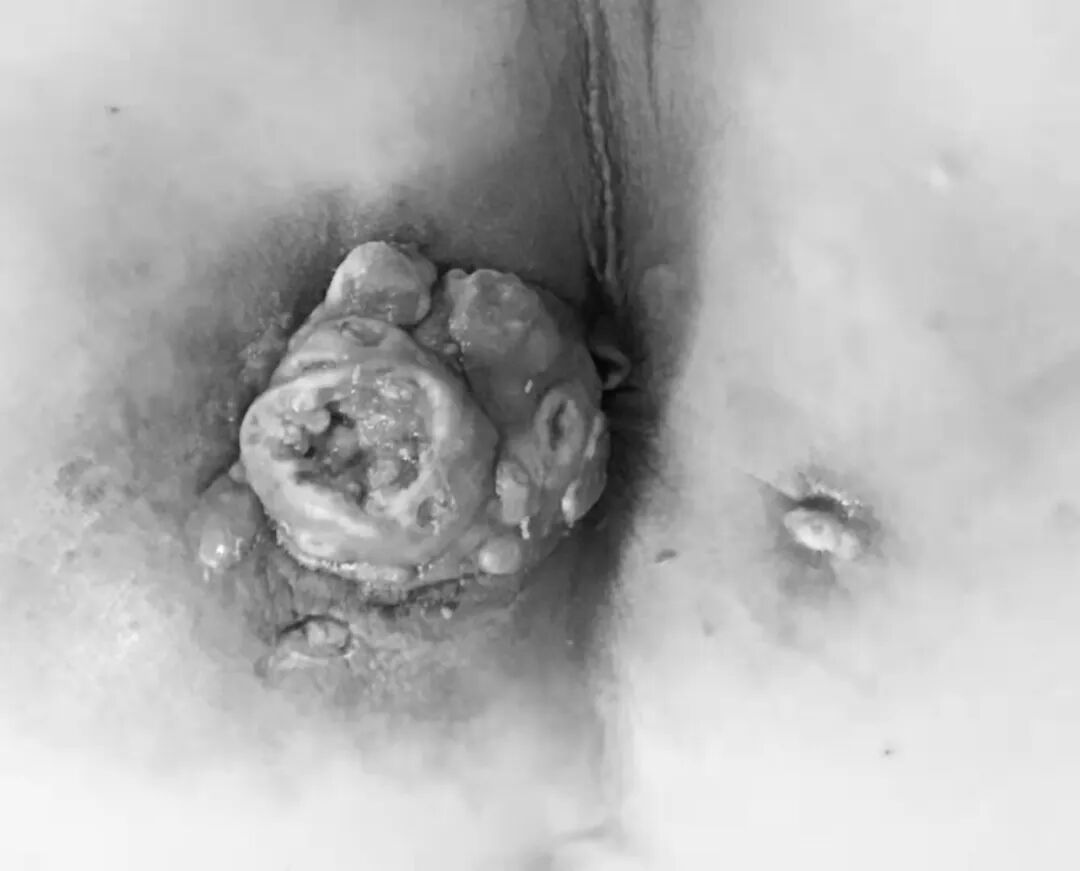

导致癌变的原因主要有两种:一种情况是,细菌长期存在于瘘管内,特别是绿脓杆菌或结核菌感染,缠绵不愈,可导致癌变。另一种情况是,长期的慢性炎症刺激。长期的炎症存在,使得脓性物质以及粪便从瘘管排出,从而刺激细胞异常增生,导致恶性病变。这是*需要患者警惕的一种并发症。

已经发生癌变的肛瘘外口